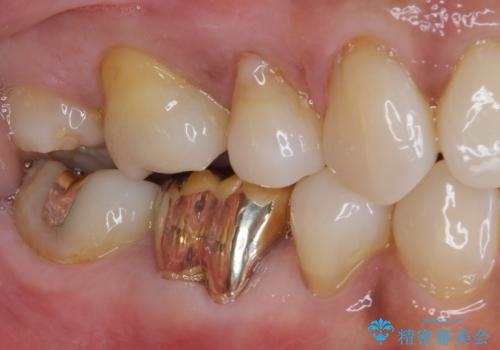

ゴールドは「白い歯」ではありませんが、銀歯の金属色とは異なり、非常にきれいな色合いが特徴です。

もちろん、適合が極めて良いという圧倒的メリットもゴールドクラウンやゴールドインレーの特徴です。